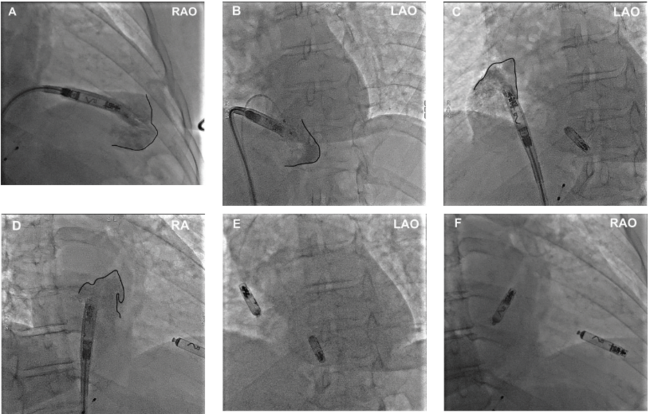

Case 1. A 69-year-old female with symptomatic paroxysmal AF despite rate control medication and class 3 antiarrhythmic medication (amiodarone) presented with symptomatic tachycardia-bradycardia syndrome, resulting in multiple conversion pauses, the longest lasting 12 seconds with presyncope. She was emergently sent to the emergency department (ED), where a temporary transvenous pacemaker was placed until timing for a dual-chamber leadless pacemaker could be coordinated. Figure 1 demonstrates AVEIR DR leadless pacemaker placement.

Li et al. Right Ventriculography Improves the Accuracy of Leadless Pacemaker Implantation in Right Ventricular Mid-septum. Reproduced with permission under CC BY 4.0. creativecommons.org/licenses/by/4.0/.15